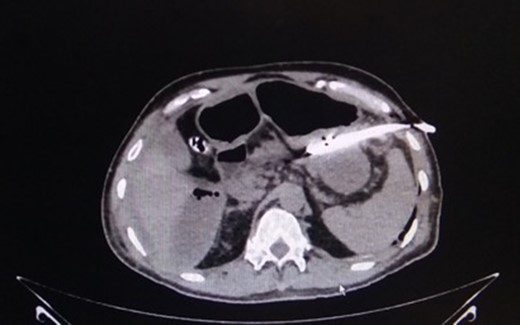

This 50-year-old male had, 4 months previously, undergone an anterior resection of a recto-sigmoid adenocarcinoma, non-anatomical resection of a liver metastasis and diverting loop ileostomy. The pathological report was a moderately differentiated adenocarcinoma and he subsequently received seven cycles of adjuvant chemotherapy. Two weeks after the last chemotherapy cycle he had a contrast study through the distal limb of his ileostomy which was normal. He then underwent a side-to-side hand sewn ileo-ileal anastomotic closure and started passing flatus and stools from the third postoperative day (POD). On POD 4 however he developed lower abdominal distension and a plain X-ray of the abdomen revealed air to be present in the colon and rectum with a few prominent small bowel loops. He then developed massive painless penoscrotal swelling, On local examination the genitals were not tender and there was no elevation of the local temperature (penoscrotal oedema image, Fig. 1). Blood investigations revealed a haemoglobin level of 12.8 g/dl, total leucocyte count of 5900/mm3, serum creatinine of 0.85 mg/dl, total protein 5.18 g/dl and albumin 2.95 g/dl. A urologist’s opinion was sought who opined that the patient might be having common iliac vein thrombosis but a Doppler study of the lower limb and pelvic veins was normal. However the abdominal distension persisted although he was passing flatus and stools. CECT of the abdomen was done on POD-6 and this revealed a large irregular air containing collection extending from the right subhepatic region along the paracolic gutter into the pelvis as well as a fluid collection in the lesser sac extending along the greater curvature of the stomach (CT images). Three percutaneous drains were then inserted—one each in the subhepatic region, pelvis and the left lesser sac and 1500 ml of faeculent content was removed. The patient was kept nil by mouth, started on parenteral nutrition and his antibiotics were upgraded. Over the next 3 days the effluent decreased and the fluid became serous. The penoscrotal oedema also subsided after 4 days (Figs 2–5). On POD-12, a CT scan of the abdomen with oral contrast was done again (CT images), which showed a decreased size of the collection and no well-defined area of extravasation or leak of contrast outside the bowel lumen. The drains were then removed, he was started on oral liquids and later put on a soft diet and discharged on POD-20.

CT-image of drain in situ draining intra-peritoneal leak contents. Source: Department of Radiology, Sir Ganga Ram Hospital, New Delhi.